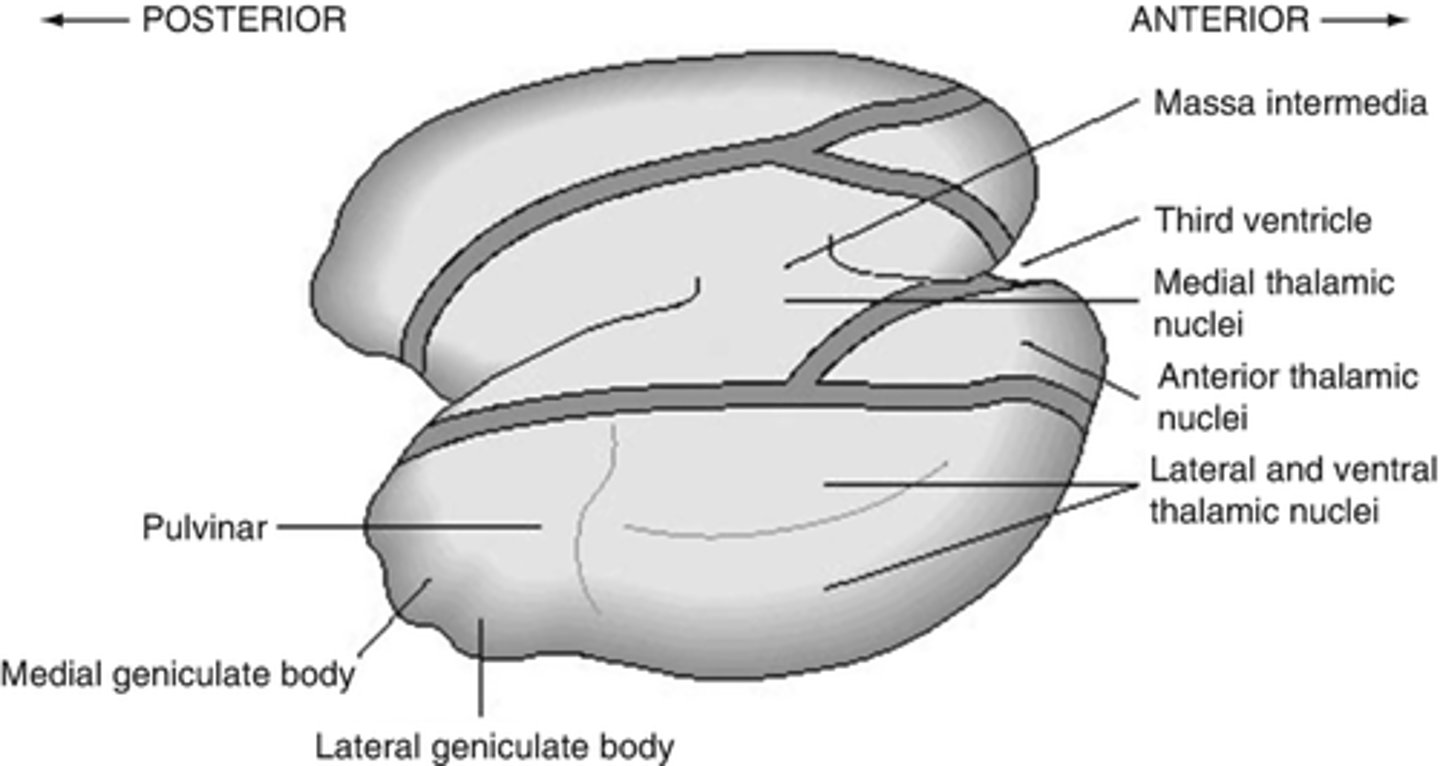

What is the massa intermedia?

the neuronal connection between the two thalami

What does the massa intermedia pass through?

3rd ventricle

What are the three nuclear complexes of the thalamus?

1. anterior nuclei

2. medial nuclei (connected by massa intermedia)

3. lateral nuclei

What are the nuclei (discussed) of the lateral nuclei of the thalamus?

1. LGN

2. MGN

3. pulvinar

4. VPL

5. VPM

What are the nuclei (discussed) of the lateral nucleus of the thalamus?

1. LGN

2. MGN

3. VPL (ventral posterolateral nucleus)

4. VPM (ventral posteromedial nucleus)

5. pulvinar

Where does the LGN project?

17 -- primary visual cortex

Where does the MGN project?

41 -- primary auditory cortex

Where does the VPL project?

3, 1, 2 -- somatosensory cortex (body)

Where does the VPM project?

3, 1, 2 near the lateral fissure -- somatosensory cortex

processing of the face

What is the pulvinar of the thalamus?

largest association nucleus of the thalamus

What is afferent to the pulvinar of the thalamus?

superior colliculus (and its association areas)

Where does the pulvinar of the thalamus project?

secondary visual areas (and association areas of the parietotemporal region)

What are the functions of the pulvinar of the thalamus?

1. attention to visual stimuli (even in peripheral vision)

2. eye movements